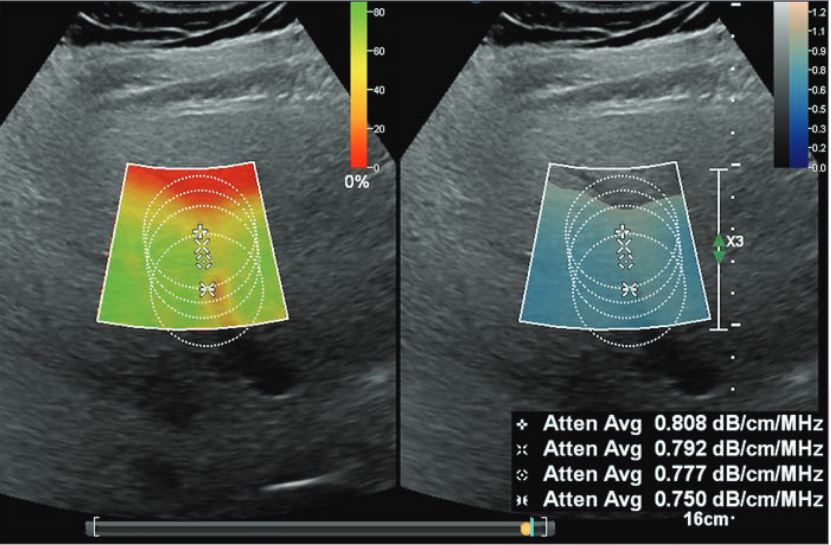

The hour-long procedure was a focal therapy treatment that targeted specific sections of the patient's prostate using ultrasound (a method called Focal One high-intensity focused ultrasound [HIFU]), Cleveland Clinic Abu Dhabi said.